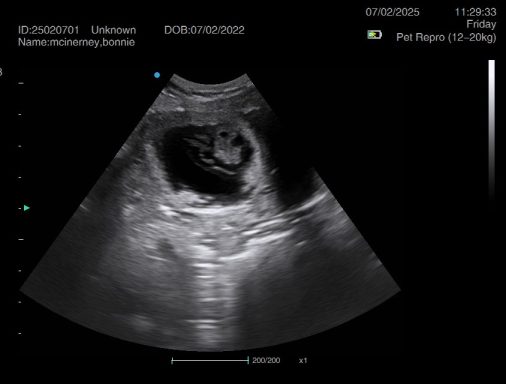

Ultrasound pregnancy scanning is a safe, non-invasive way to confirm pregnancy in dogs and cats, offering breeders and pet owners peace of mind and vital information to support responsible care. It allows us to detect gestational sacs, assess foetal development, and estimate litter size—all while ensuring the wellbeing of the animal.

Pregnancy can sometimes be detected as early as Day 18 post-mating, but scanning at this stage is not routinely recommended. Embryos are still developing and may not be clearly visible, and there is a natural risk of embryo resorption, which can lead to misleading or inconclusive results.

For the most accurate and reliable scan, we advise booking between Day 25 and Day 32, when pregnancy is more easily confirmed and foetal structures are clearer. If an early scan is performed and no pregnancy is detected, we offer a FREE complimentary re-scan after 7 days at the clinic to ensure clarity and support informed decision-making.